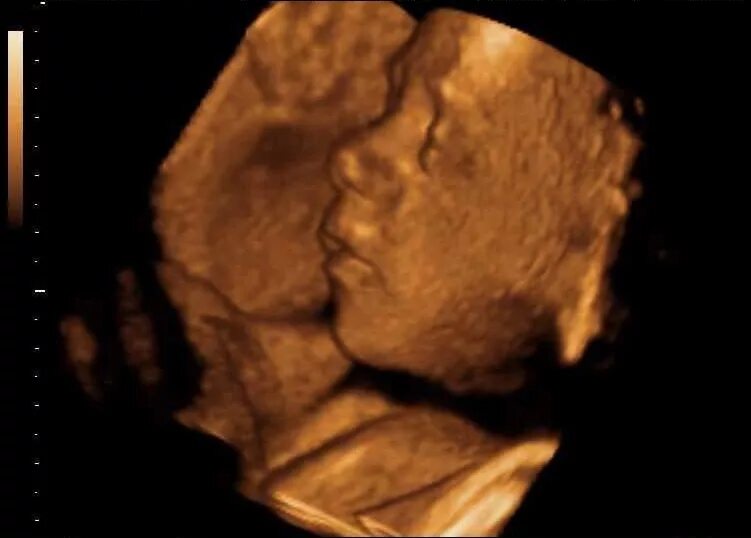

Плод на 31 неделе беременности. ребенок в животе 31 неделя.Эмбрион 31 неделя беременности. малыш на 31 неделе беременности.Плод на 31 неделе беременности. эмбрион 31 неделя беременности. малыш в утробе 31 неделя беременности.Малыш на 31 неделе беременности. малыш в животике 28 недель. малыш в утробе 31 неделя.Младенец в утробе. малыш в утробе 31 неделя. ребёнок на 31 неделе беременности.Плод на 31 неделе беременности. ребёнок на 31 неделе беременности. малыш в утробе 31 неделя. младенец на 31 неделе беременности.Плод на 31 неделе беременности. 30-31 неделя беременности. эмбрион 31 неделя беременности. 31 акушерская неделя беременности.Малыш на 31 неделе беременности.Плод на 31 неделе беременности. расположение ребёнка в утробе матери на 29 неделе.30-31 неделя беременности. ребёнок в матке на 31 неделе. плод на 31 неделе беременности.Плод ребенка. ребёнок на 31 неделе беременности.Плод на 31 неделе беременности. малыш в утробе 31 неделя беременности. ребёнок в 30 недель беременности. ркбкеок на 30 неделе беременности.Плод на 31 неделе беременности. малыш на 31 неделе беременности.Эмбрион леннарт нильсон. плод на 31 неделе беременности. леннарт нильсон фотографии.Малыш на 31 неделе беременности. ребёнок на 31 неделе беременности в животе. малыш в утробе 31 неделя беременности.Узи плода 31 неделя беременности. узи беременности 30-31 неделя. узи 31 неделя беременности мальчик. 31 неделя беременности узи фото.Узи на 33 неделе беременности мальчик. снимок узи на 31 неделе беременности. узи 31 неделя беременности мальчик.Плод на 31 неделе беременности. расположение ребенка в утробе матери на 30 недели беременности. расположение плода на 31 неделе беременности. малыш в утробе матери 31 неделя беременности.Узи плода 31 неделя беременности. 31 неделя беременности фото узи ребенка. снимок узи на 31 неделе беременности. узи беременности 30-31 неделя.Плод на 31 неделе беременности. 31 неделя беременности фото плода. плод ребенка в 31 неделю беременности. малыш на 31 неделе беременности.Плод на 30 неделе беременности. плод ребенка на 30 неделе беременности. ребёнок в 30 недель беременности. 31 неделя беременности фото плода.31 неделя беременности как выглядит31 неделя беременности фото плода на узи. 3д узи 31 неделя беременности девочка. 3д узи на 31 неделе беременности.Узи 31 неделя беременности. узи плода 31 неделя беременности. 31 неделя беременности узи фото. эмбрион на 30 неделе беременности узи.Ребёнок на 31 неделе беременности. узи хомиладорлик.Узи ребенка на 31 неделе беременности. 32 недели беременности фото плода на узи. 31 неделя беременности фото плода на узи. снимок узи 32 недели беременности.Малыш в животике на 32 неделе. ребёнок на 31 неделе беременности. 31-32 неделя беременности.Живот на 31 неделе беременности. животик на 31 неделе беременности. ребёнок на 31 неделе беременности в животе.Живот на 31 неделе. животик на 31 неделе беременности. беременный живот на 31 неделе.Беременность 29 недель положение плода. ребенок в животе на 25 неделе. плод на 32 неделе беременности. матка на 21 неделе беременности.Малыш в утробе 32 неделе беременности. плод 31-32 недели беременности. ребёнок на 32 неделе беременности в утробе. плод в 32 недели беременности в животе.Живот на 31 неделе. живот на 30-31 неделе. живот на 31 неделе беременности животик.Ребёнок на 24 неделе беременности. оебнок на 24 неделе беременности. новорожденный ребенок на 24 неделе беременности.Ребёнок 30 неделя беременности в утробе. малыш в утробе 31 неделя беременности.Ребенок в 32-33 недели беременности. плод на 33 неделе беременности. ребенок на 33 неделе беременности. малыш на 33 неделе беременности.Ребёнок в 34 недели беременности в утробе. 32 недели беременности фото плода. малыш в утробе 32 неделе беременности. ребёнок в 32 недели беременности в животе.Ребёнок на 32 неделе беременности. новорожденный в 35 недель.Малыш на 31 неделе беременности. новорожденный ребенок 31 неделя. рождение ребенка на 31 недели беременности.31 неделя беременности как выглядитПлод на 34 неделе беременности картинки. 34 неделя беременности фото плода. 34 эмбриональная неделя беременности. плод ребенка в 34 недели беременности.